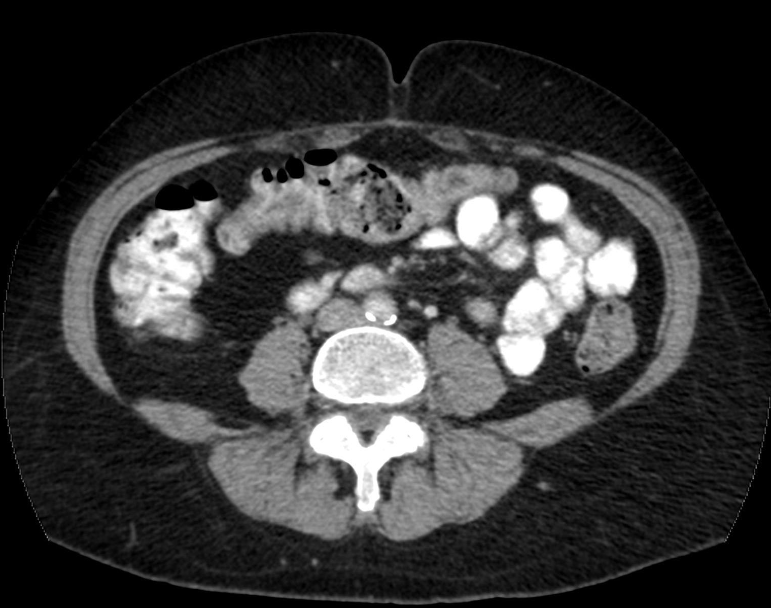

what is computed tomography?

passes x-rays through body at large number of angles

done by rotating x-ray tube around patient

how are these images produced in CT?

computer synthesizes the data into tomographic images

tomographic images eliminate superposition of anatomical structures

you get unobstructed view of the anatomy